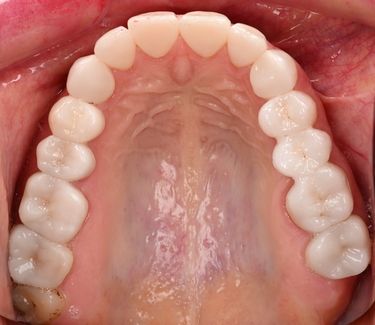

Figure 13: Upper jaw - after

Figure 15: Lower jaw - after